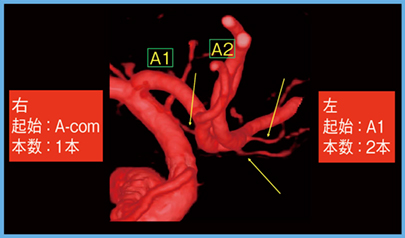

4.Heubner反回動脈

Heubner反回動脈は,前大脳動脈のA1/A2 junction付近から起始し,A1に並走するように反回する穿通枝動脈であるが,起始部や本数にバリエーションがある。閉塞により,顔面や上位優位の半身麻痺,失語が出現するため,前交通動脈瘤の術前に起始部や本数を同定することが重要である。Aquilion Precisionでは,Heubner反回動脈を明瞭に描出でき,起始部や本数を確認することができる(図6)。

図6 Heubner反回動脈